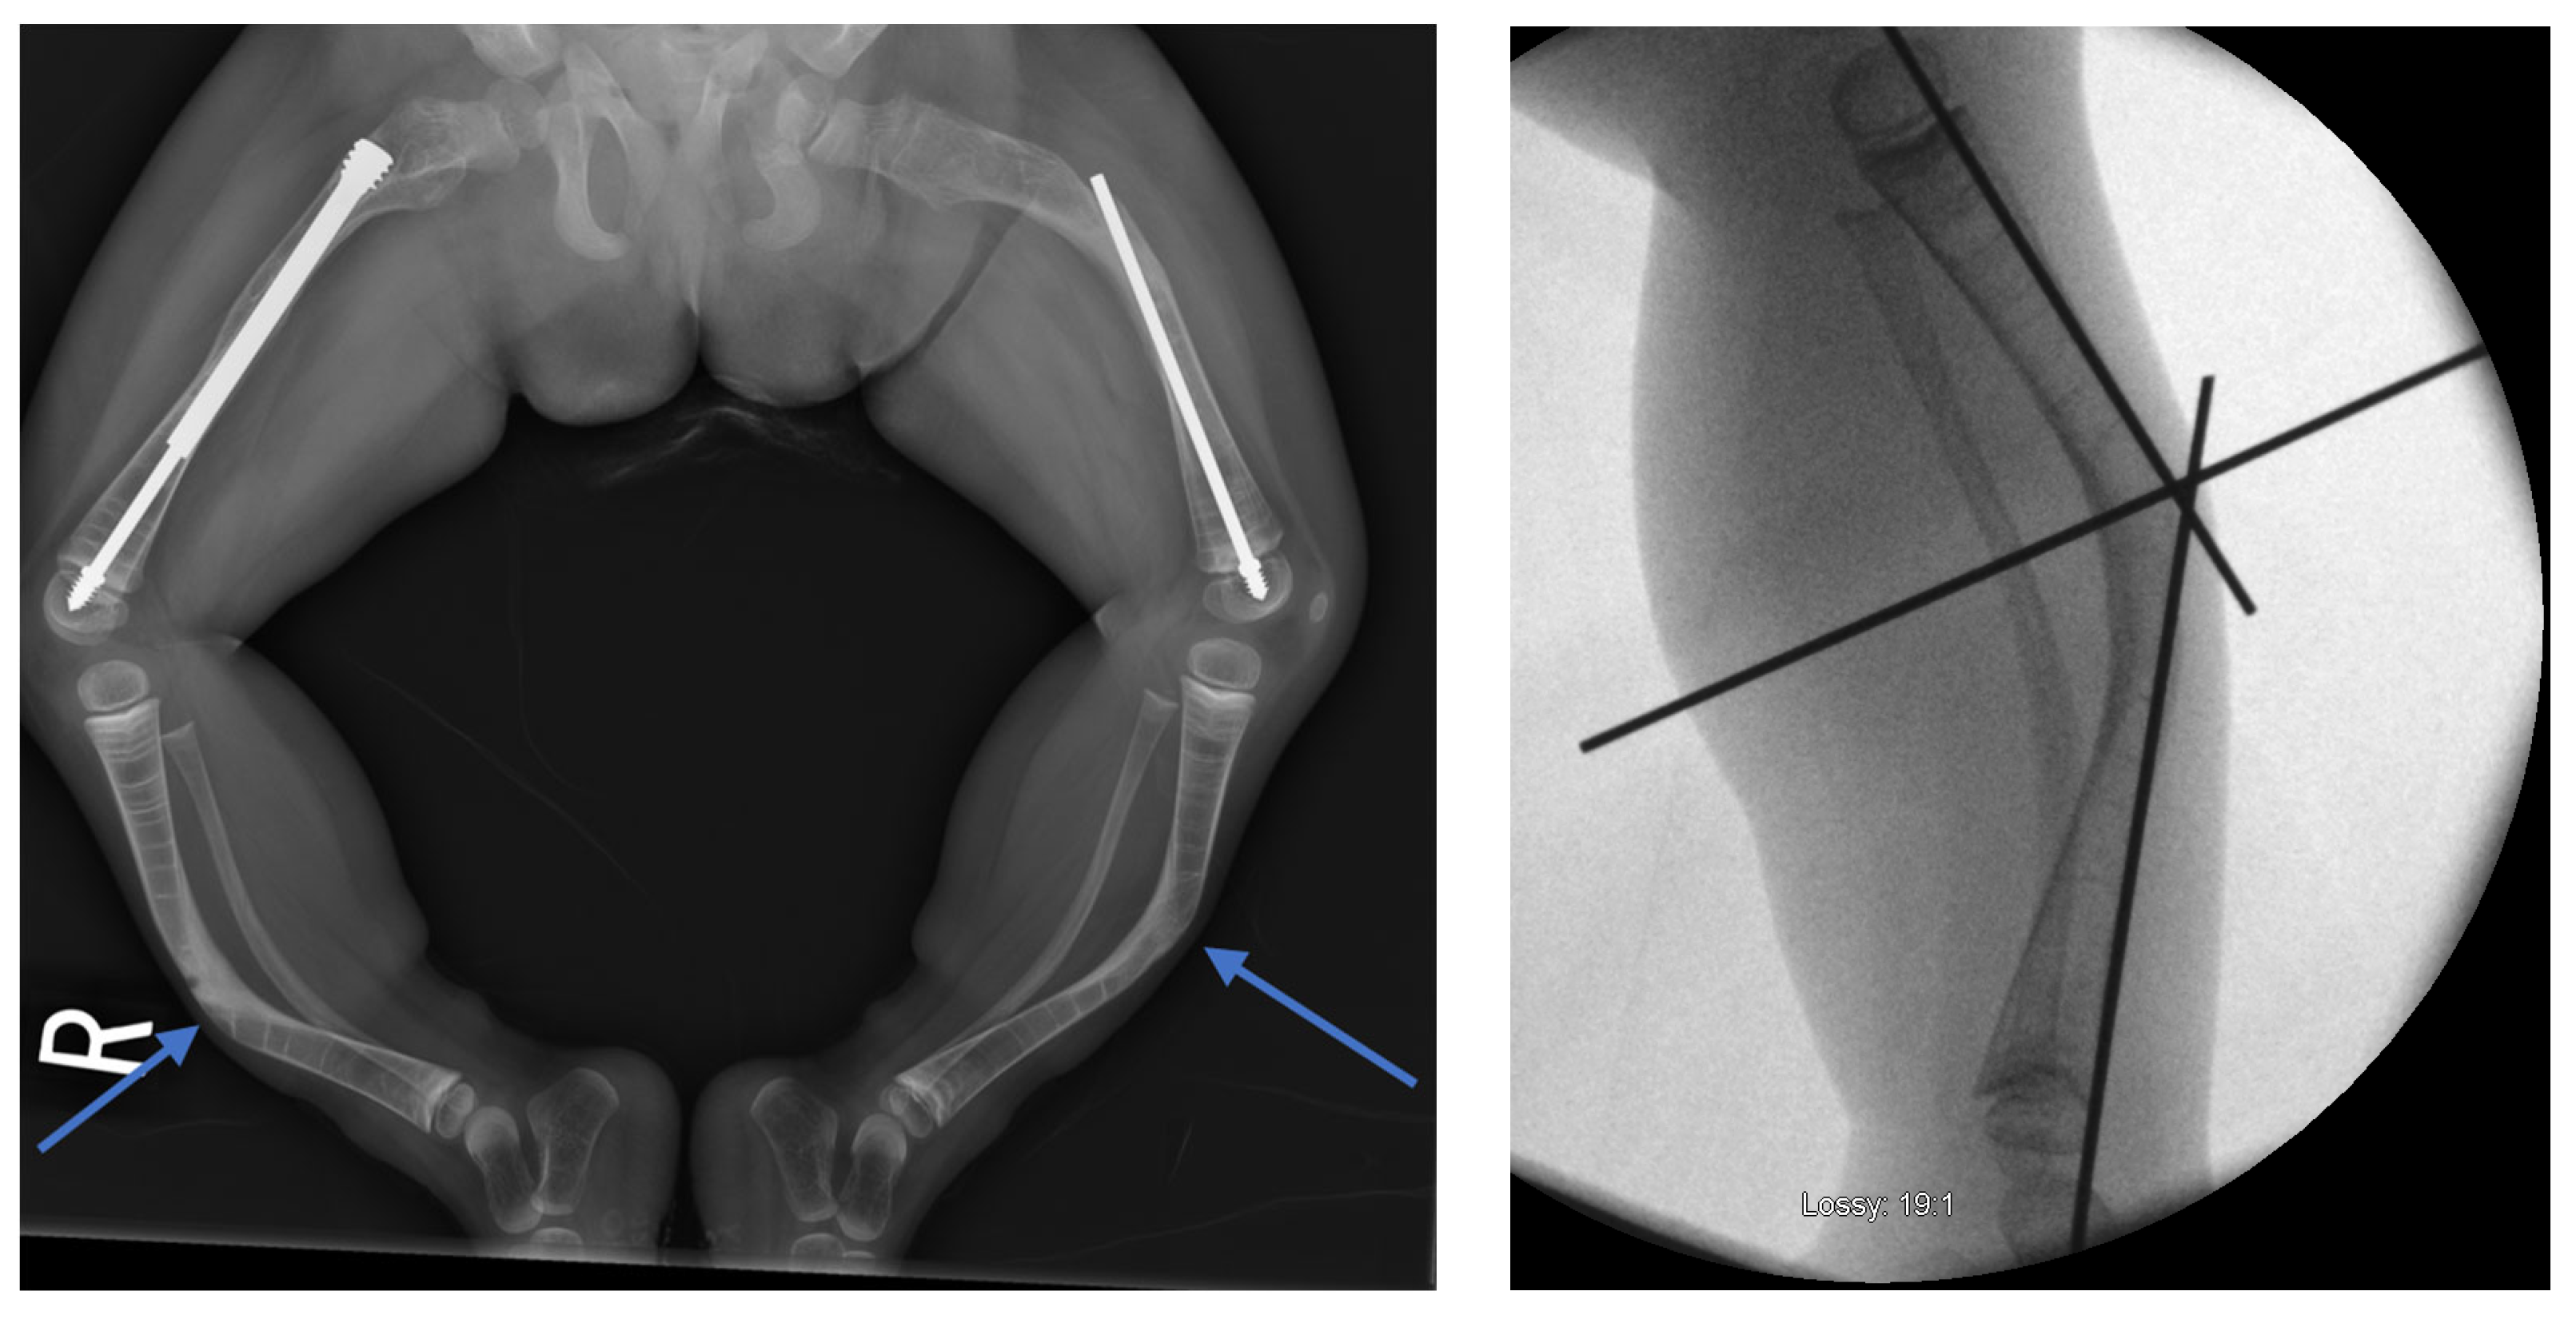

2.4. Reaming and Nail Insertion

Once the osteotomy is complete, the two bone segments can be reduced to ensure proper alignment (Figure 7a). Reaming can then be performed retrograde into the proximal bone segment through the osteotomy site, and antegrade into the distal bone segment (Figure 7b–d). Under fluoroscopy, external K-wires or SLIM nails are used to measure the required nail length, which is subsequently verified with the actual nail before insertion. Finally, the nail is inserted, positioned centrally in the canal, and advanced until the proximal threads anchor in the epiphysis (Figure 7e). The technique described above and in Figure 7 describes the retrograde approach. In cases with mild deformity (less than 20 degrees in the coronal or sagittal plane) a mini invasive percutaneous osteotomy could be performed, and in such cases, an antegrade approach could be used, in which the insertion of the guide wire, reaming, and insertion of the SLIM nails are all performed through the proximal entry points.

Figure 7.

Intramedullary reaming and SLIM nail insertion. Blue arrows indicate the direction of reaming and nail insertion. (a) Osteotomy is complete. (b) Lateral view of proximal reaming via the osteotomy site. (c) AP view of proximal reaming via the osteotomy site. (d) AP view of distal reaming via the osteotomy site. (e) Insertion of the SLIM nail.